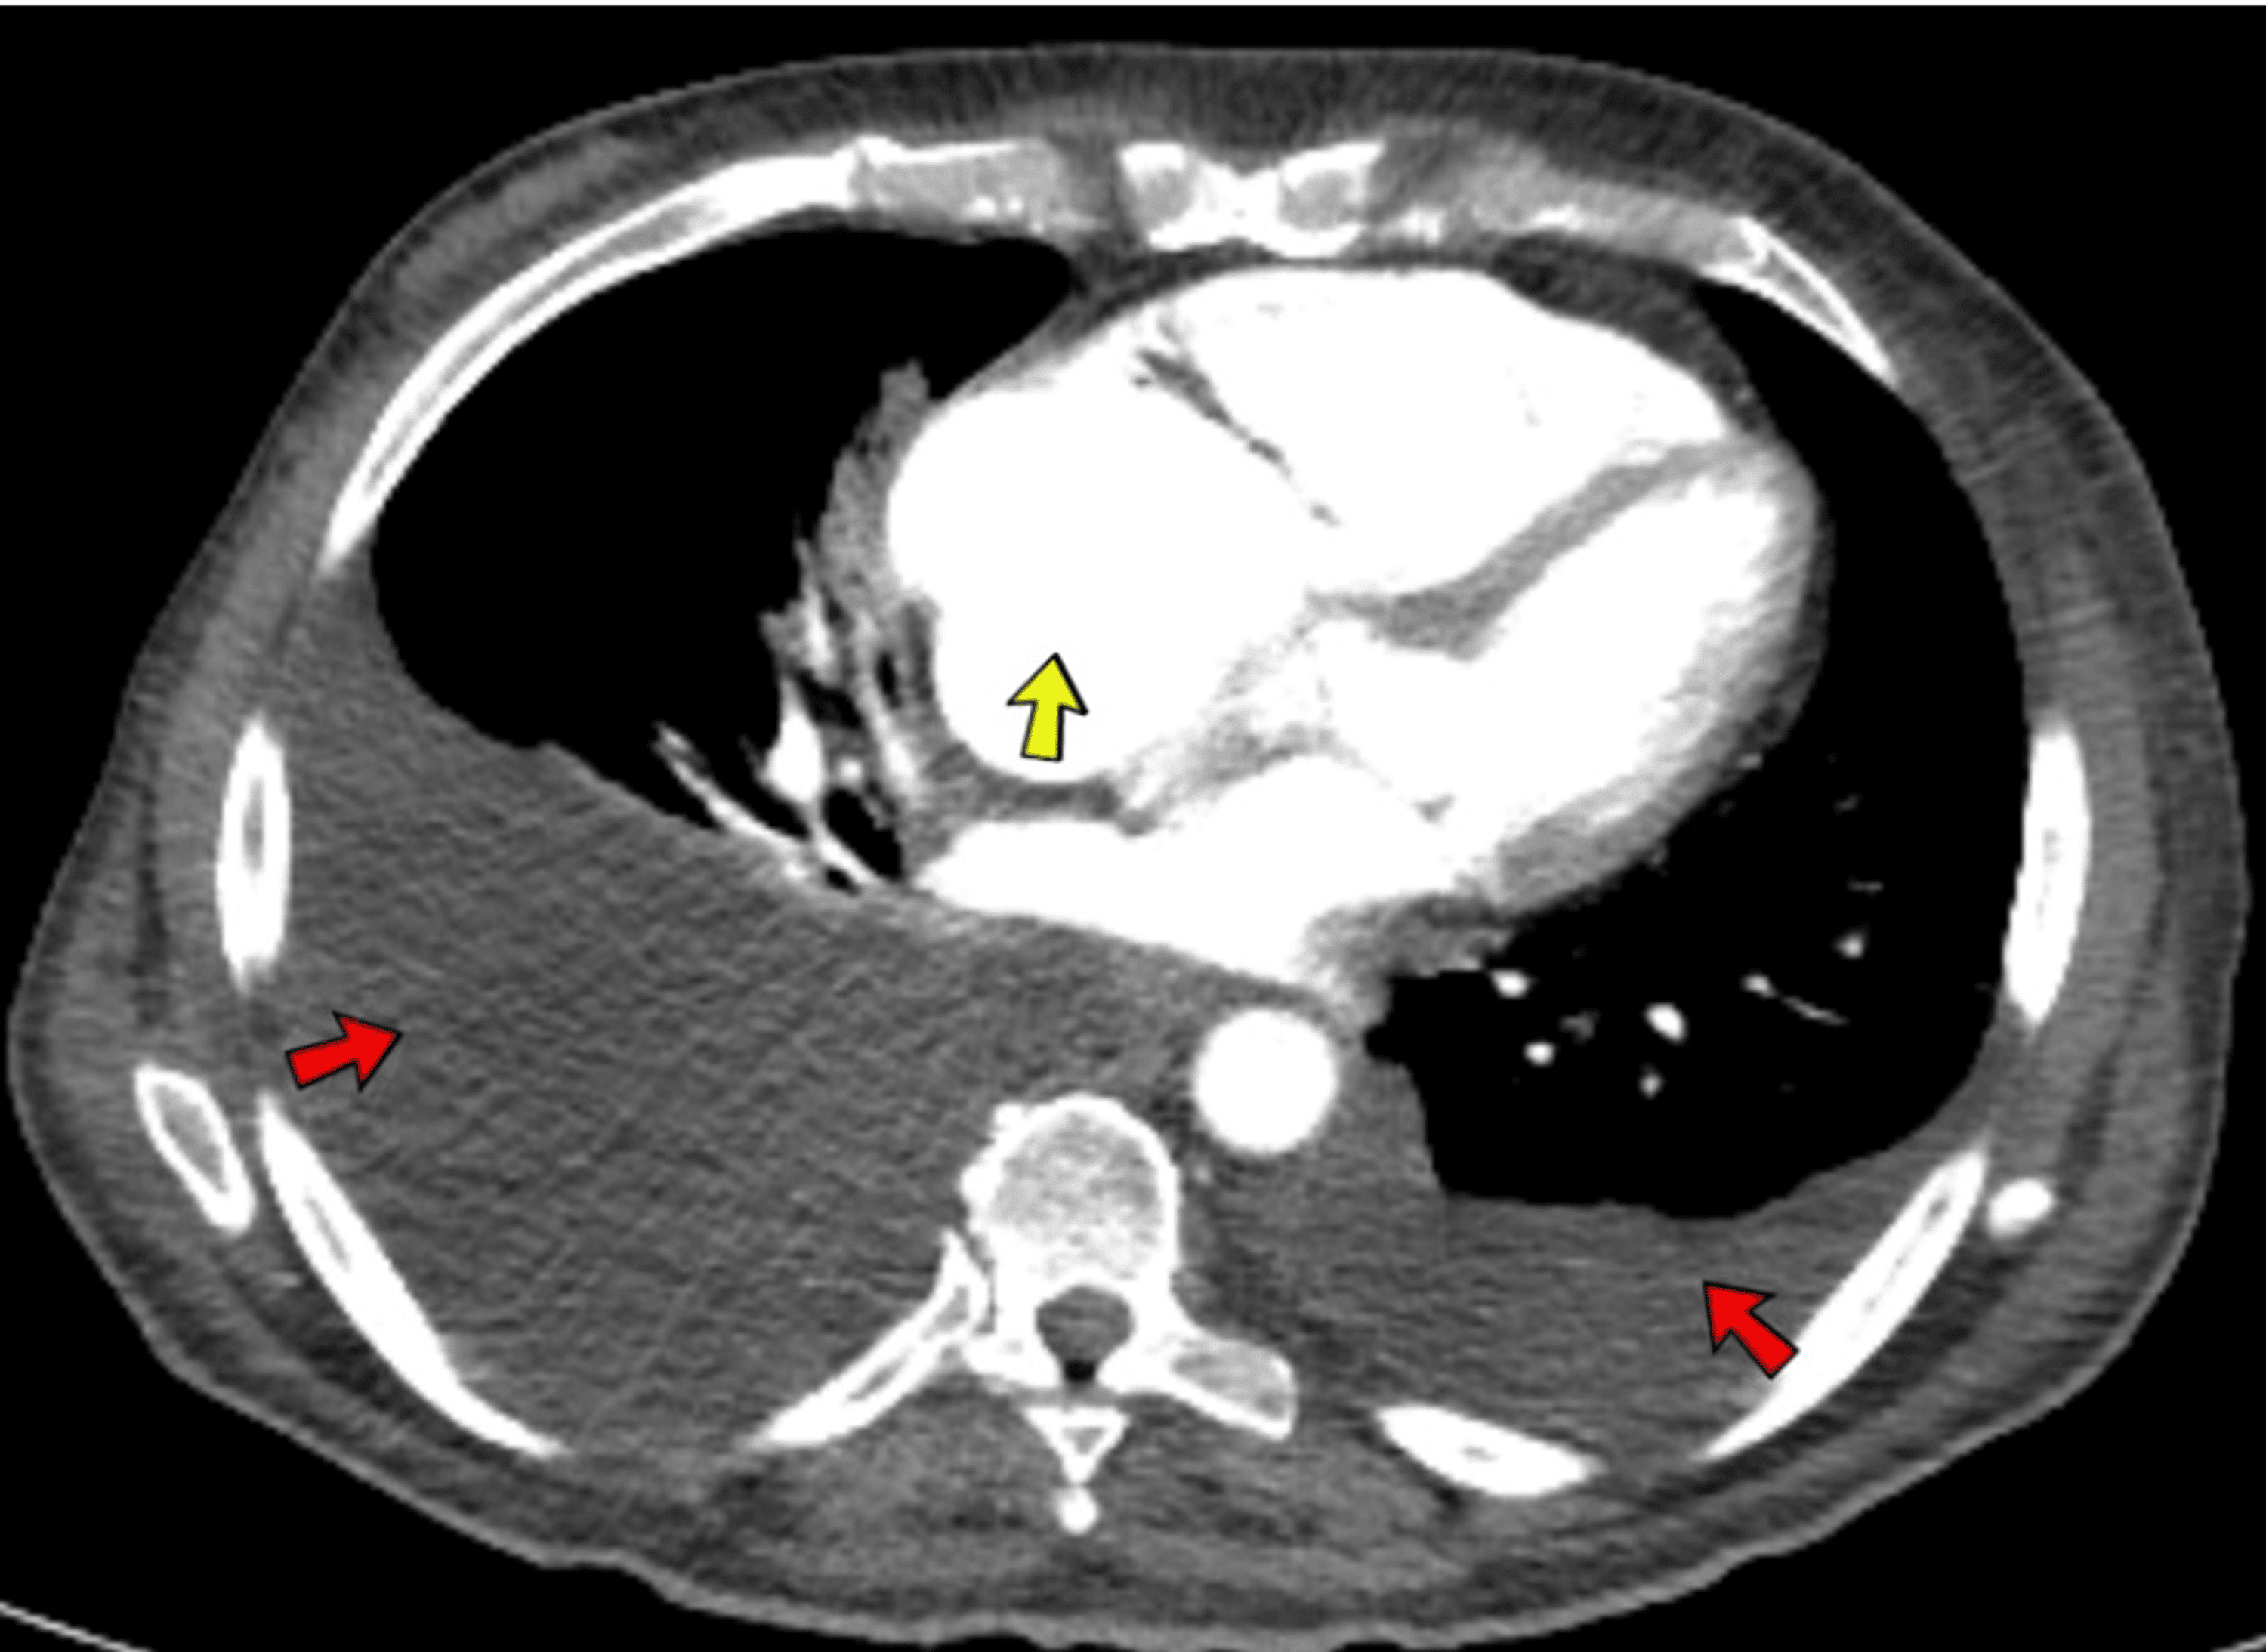

From www.cureus.com

Carcinoid Heart Syndrome With Metastatic LowGrade Neuroendocrine Tumor What Is Borderline Enlarged Heart An enlarged heart (cardiomegaly) means that your heart is bigger than normal. It usually doesn’t cause symptoms, so it’s usually only detected. Your heart can become enlarged when it. An enlarged heart, also known as cardiomegaly, can lead to serious health problems such as heart failure, stroke, or even sudden death. Mild cardiomegaly, or an enlarged heart, is usually a. What Is Borderline Enlarged Heart.

Carcinoid Heart Syndrome With Metastatic LowGrade Neuroendocrine Tumor What Is Borderline Enlarged Heart An enlarged heart (cardiomegaly) means that your heart is bigger than normal. An enlarged heart, also known as cardiomegaly, can lead to serious health problems such as heart failure, stroke, or even sudden death. Your heart can become enlarged if the muscle works so hard that it thickens, or if the chambers. Mild cardiomegaly, or an enlarged heart, is usually. What Is Borderline Enlarged Heart.

Carcinoid Heart Syndrome With Metastatic LowGrade Neuroendocrine Tumor What Is Borderline Enlarged Heart An enlarged heart (cardiomegaly) can be caused by damage to the heart muscle or any condition that makes the heart pump harder than usual, including pregnancy. An enlarged heart, also known as cardiomegaly, can lead to serious health problems such as heart failure, stroke, or even sudden death. It usually doesn’t cause symptoms, so it’s usually only detected. Your heart. What Is Borderline Enlarged Heart.